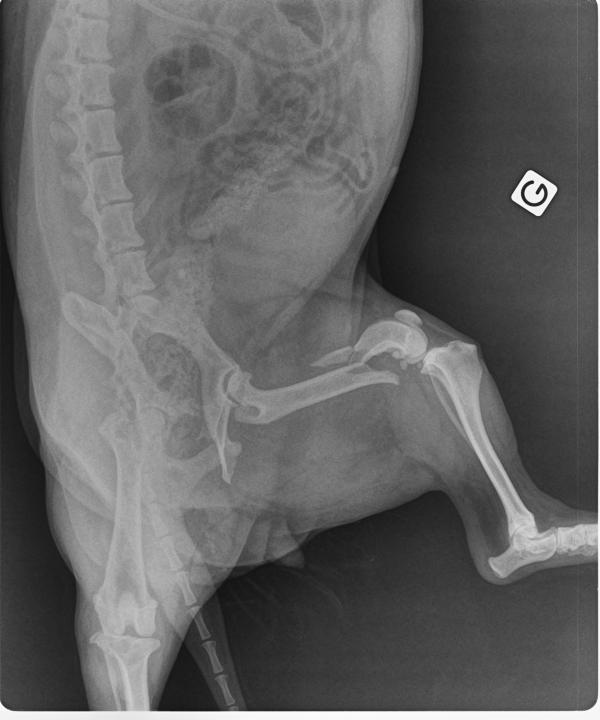

Uma vez identificada a dor no joelho, devemos transferir nosso cão para o veterinário, que pode diagnosticar o rompimento realizando um exame físico por palpação do joelho, como acontece com o chamado teste da gaveta. Além disso, com um raio-x você pode avaliar o estado dos ossos do joelho. Os dados que fornecemos também ajudam no diagnóstico, por isso, devemos informá-lo quando o cachorro começou a mancar, como ele manca, se isso diminui com o descanso ou não, ou se o cão sofreu um golpe recente. Devemos saber que é característico do rompimento do ligamento cruzado em cães começar com muita dor, que irá diminuir até que o rompimento afete todo o joelho, momento em que a dor retorna devido ao dano resultante da quebra, como a artrose.

Este problema é relativamente frequente e grave, e pode afetar cães de todas as idades, especialmente se excederem os 20 kg de peso. É produzido por um rompimento repentino ou por uma degeneração. Os ligamentos são elementos que ajudam a estabilizar as articulações. No joelho dos cães encontramos dois ligamentos cruzados: o anterior e o posterior, porém, o que tende a se romper com maior frequência devido à sua posição é o anterior, que une a tíbia ao fêmur. Então, seu rompimento, neste caso, causa instabilidade no joelho.

Às vezes, a ruptura do ligamento também danifica o menisco, que é como uma cartilagem que amortece as áreas onde dois ossos devem ser articulados, como é o caso do joelho. Portanto, quando o menisco é lesionado, a articulação será afetada e pode ficar inflamada. A longo prazo, haveria artrite degenerativa e coxeira permanente se não for tratada. Os ligamentos laterais também podem ser afetados.